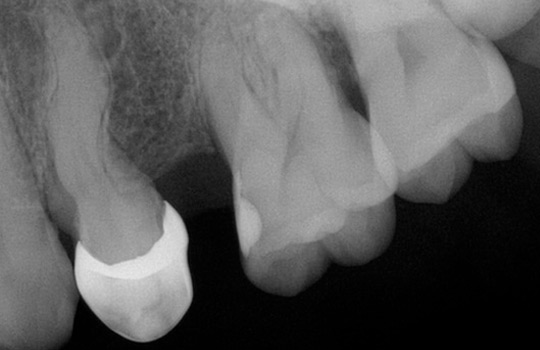

Tratamiento que se realiza con la finalidad de salvar un diente. De no ser tratado tendría que ser extraído; necesario cuando un trauma o caries daña al tejido interno del diente (pulpa).

El tratamiento consiste en la eliminación del tejido pulpar dañado, así como la desinfección y el sellado para poder recibir una prótesis y evitar futuras infecciones.